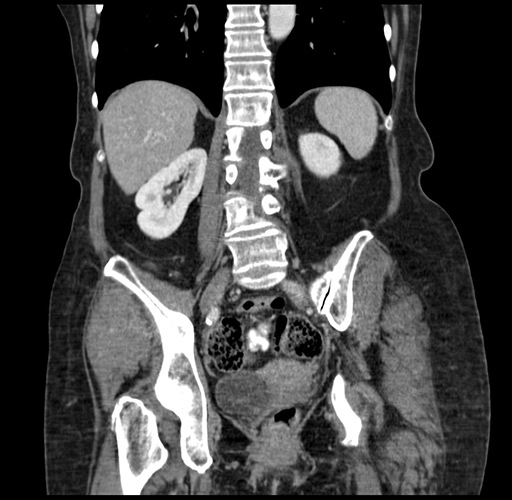

Pre-Chemo: Coronal Venous

Coronal Venous